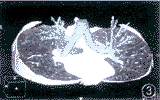

图3 气管支气管3D图像,可显示段和部分亚段支气管, 肺组织切面同时以MPR方式显示